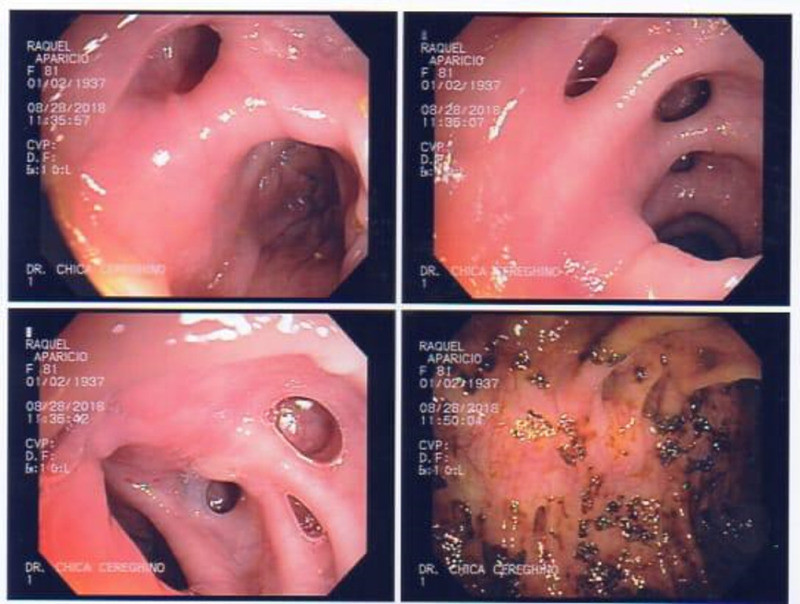

Paciente con várices esofágicas